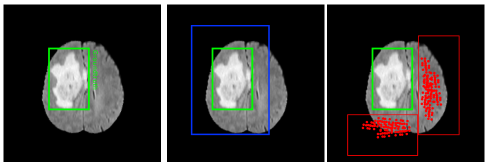

Figure 1: Illustration of contextual detection. From left to right: Given an image with groundtruth (left), positive window is defined as contextual around groundtruth (middle) and negative windows which are not covered in the positive windows (right). Each red circle is corresponding to center of each proposal.

Positive windows generation: Different from p𝑝p positive chips selection in SNIPER [24], groundtruth proposals in our detection network are created by union regions of whole tumor (WT), tumor core (TC) and enhance tumor (ET). Thus, the positive window is defined as a contextual region around the groundtruth and the size of the positive window is as twice as brain tumor groundtruth. An example of positive windows generation is given in Fig.1(middle) where the groundtruth is presented in green box and the positive window is presented in blue box.

Negative Windows Generation: Although the positive windows cover all the positive proposals, a significant portion of the brain, which is not lesion and maybe considered to be background, is not covered by them. Compare to the lesion region, the background including brain background and black background is much bigger. In order to avoid high computation, a simple approach is to employ object proposals to identify regions where objects are likely to be present. In this step, we eliminate regions that does not contains any object, simply the almost black background will be ignored. Notably, object in this scenario is brain background but not brain tumor. In order to obtains negative windows, we first train a RPN which is setup as same as Faster-RCNN [28] for small number of epoches over the entire training set to roughly guide us in selecting regions which are likely to contain false positives. If no proposals are generated in a major portion of the image by RPN, then it is unlikely to contain an object instance. At each scale, to generate negative windows, we first eliminate all the proposals which have been covered in the positive windows in the previous step, then greedily select all the windows which cover at least P𝑃P proposals (P𝑃P is chose as 2 in our experiments). An example of negative windows generation is given in Fig.1(right) where the groundtruth is presented in green box and the negative window is presented in red box which are not covered in the positive windows. Each red circle is corresponding to center of each proposal.